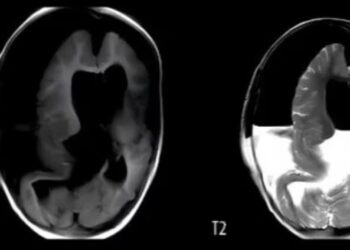

Se trata de una condición extremadamente rara que se conoce como FIF. Los médicos indicaron que la mayoría de los ...